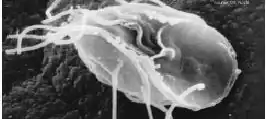

Trofozoïet van Giardia lamblia

Giardiasis is een infectie van de dunne darm die veroorzaakt wordt door Giardia lamblia, ook wel Giardia duodenalis of Giardia intestinalis genoemd: een eencellige. De ziekte heeft diarree als belangrijkste symptoom. Giardiasis is wereldwijd een van de meest voorkomende oorzaken van diarree, zowel bij mensen als bij dieren.